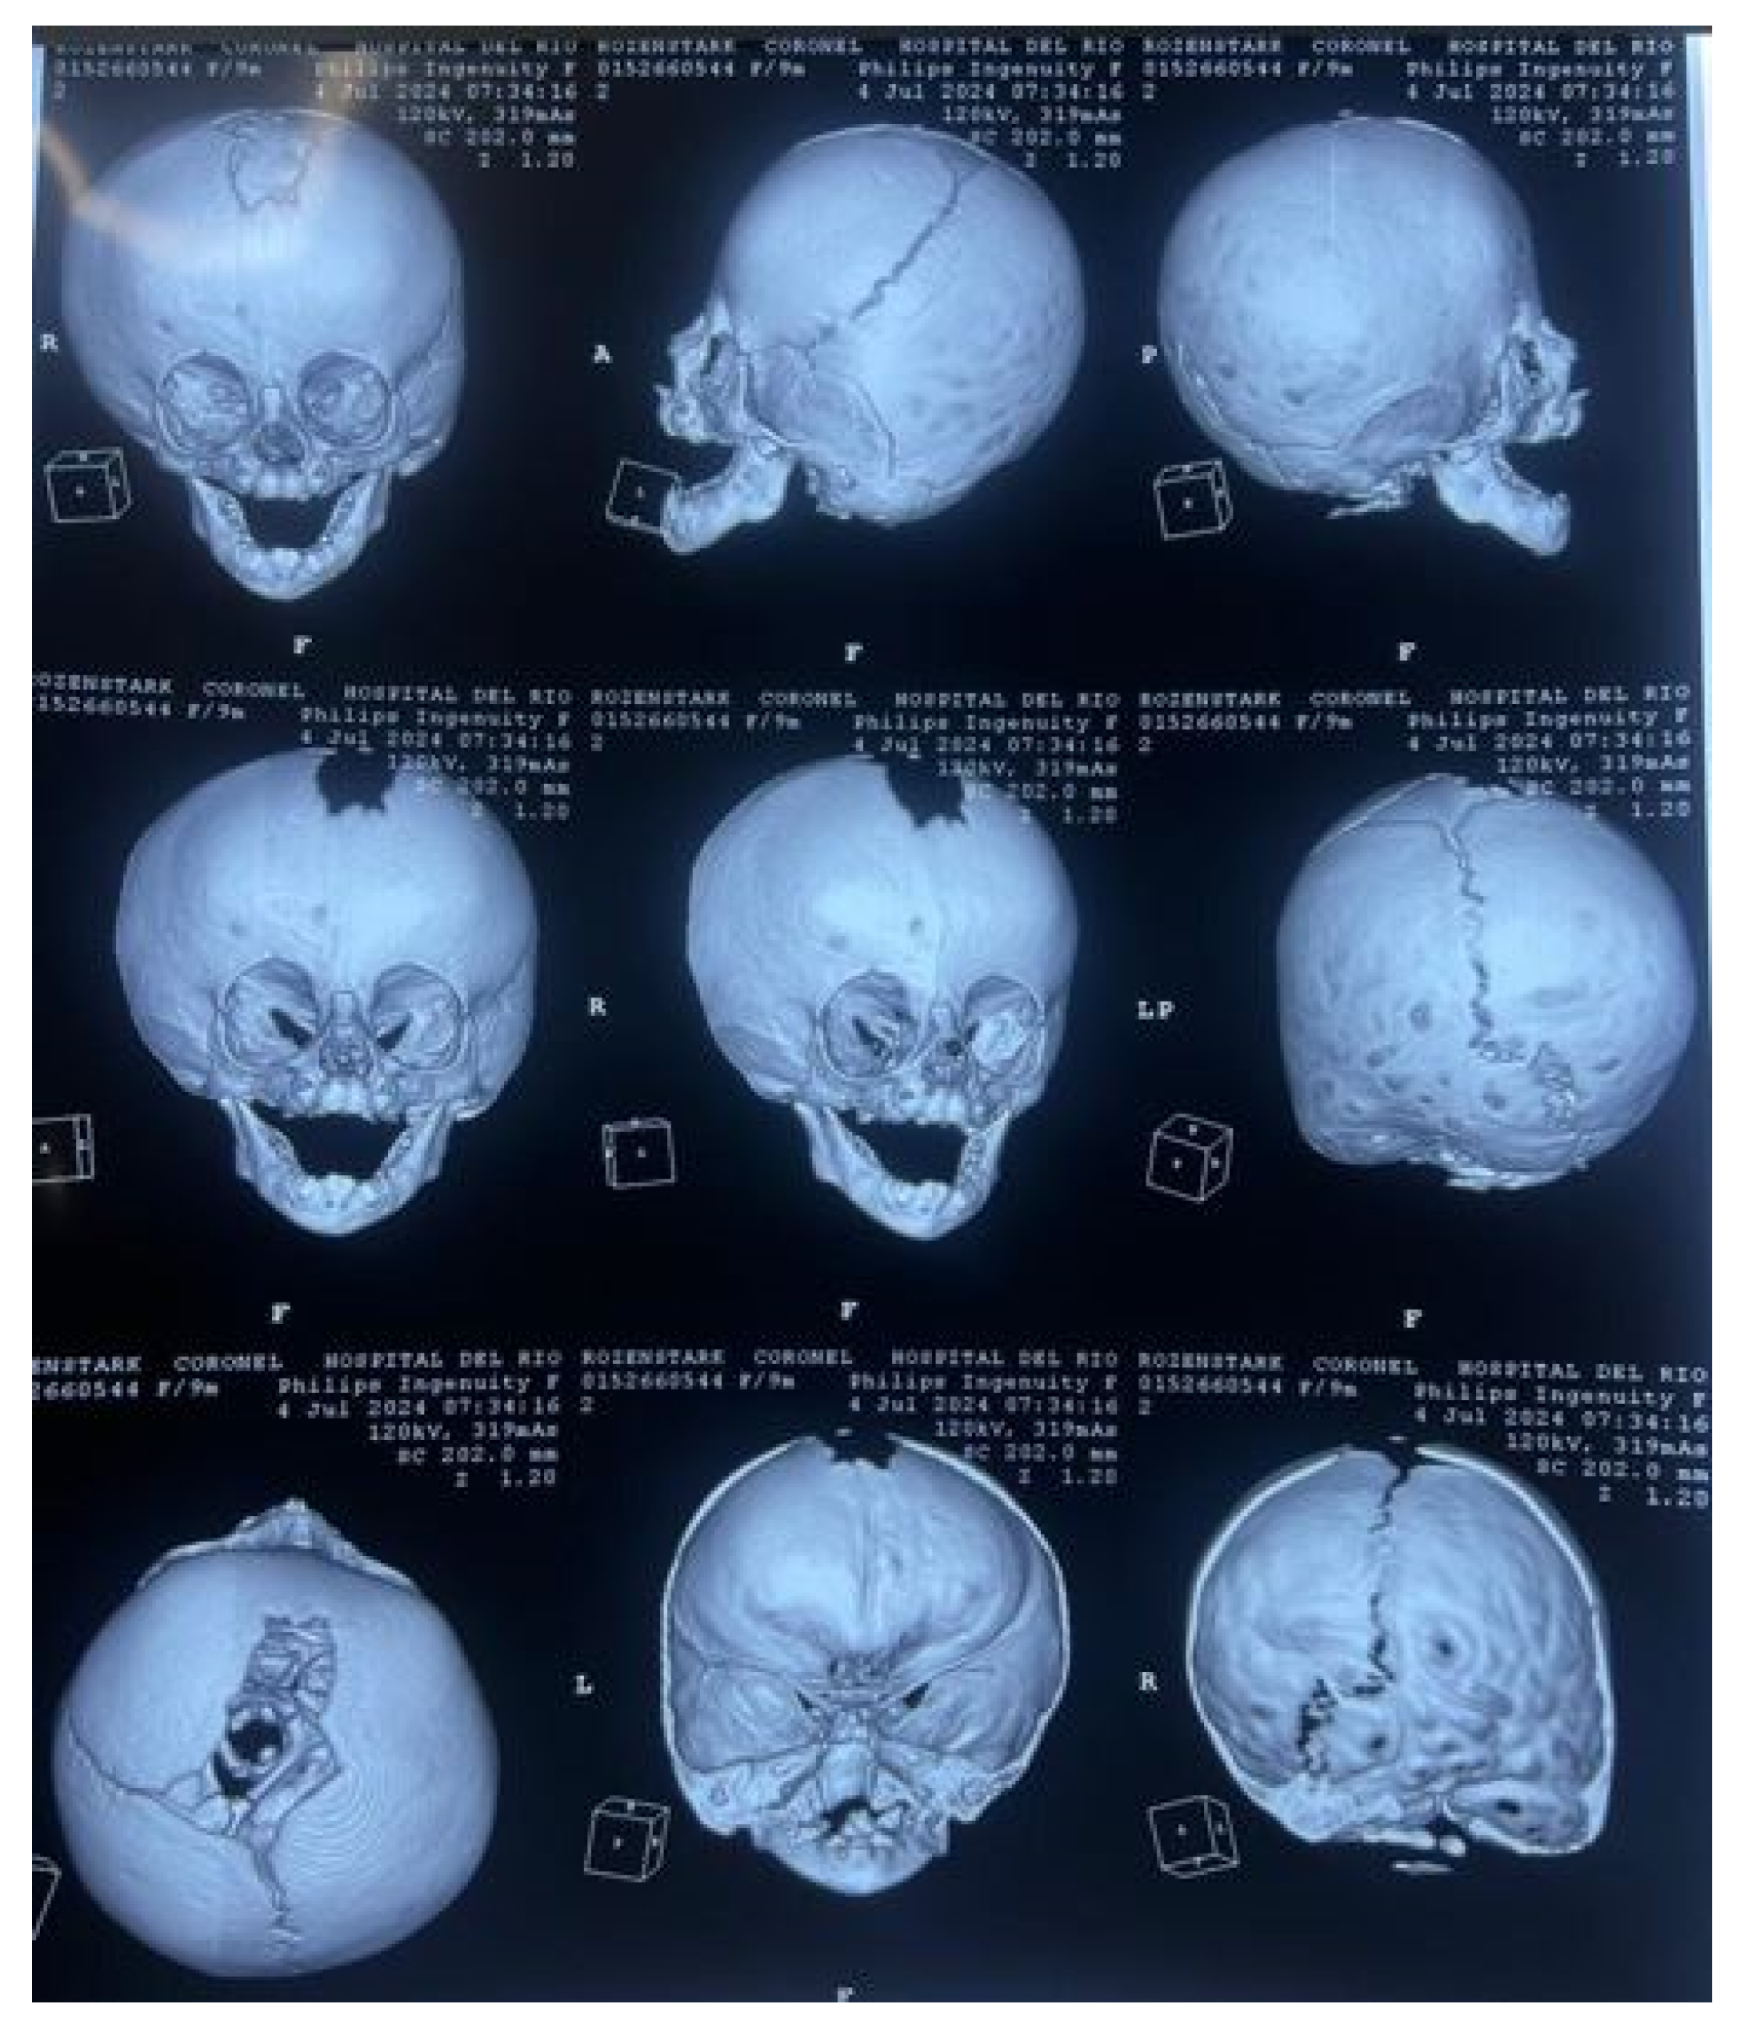

3.7.1. Diagnosis and Analysis

3.7.2. Surgical Planning